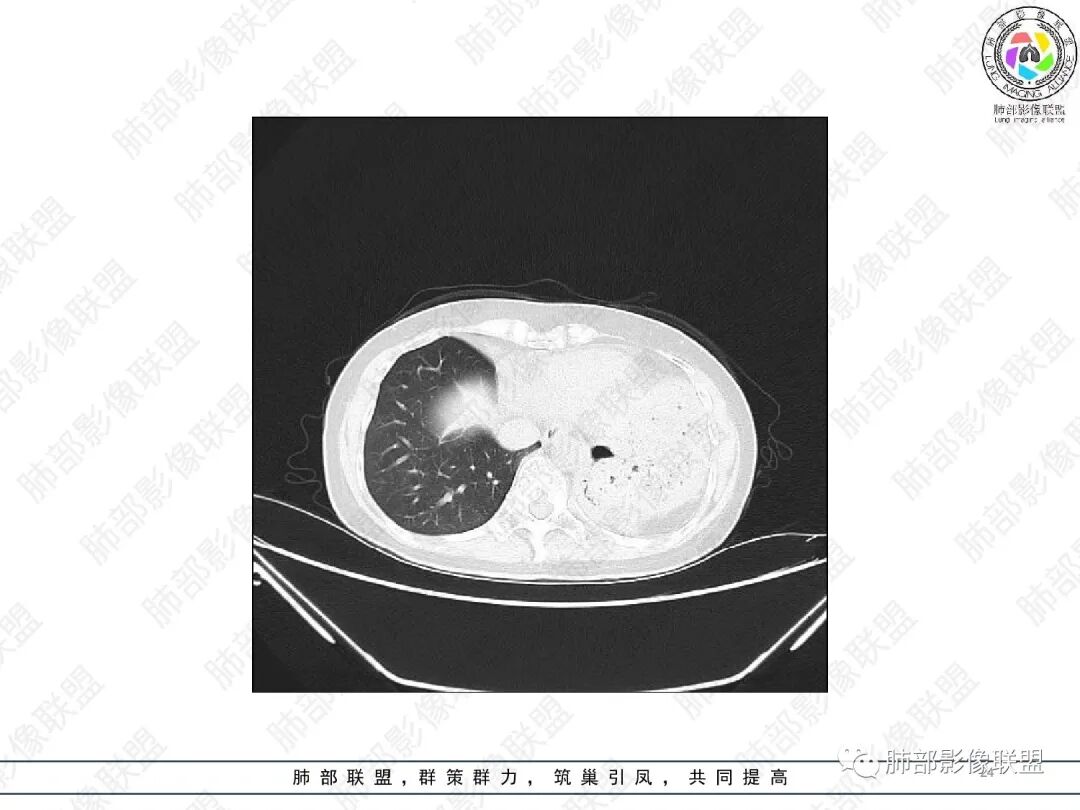

女,51,咳嗽、咳痰半年。左下叶手术史,术后抗TB治疗史。胸部CT:右肺上叶尖段团片影,边界较清,部分层面周围清楚GGO;形态不规则,近端呈指套样改变;密度不均,内见斑点状高密度灶;胸膜牵拉。右肺中叶内侧段斑片实变影,邻近多发小树芽影?左侧胸廓塌陷,左上叶多发小结节影,支气管扩张样改变,左上叶支气管腔可见钙化影。考虑TB,鉴别ABPA、腺Ca等。

2.胸部CT:右肺上叶及中叶不规则块状影,沿支气管走行方向指套样影,支气阻塞湖嵌塞,腔内可见高密度影。灶周可见磨玻璃,外围见结节影及树芽征。左肺体积缩小,见不规则条索影、胸膜增厚,纵隔牵拉左移。

胸部影像学的特异性改变:随着胸部高分辨率CT(HRCT)的普及,ABPA常见肺部影像表现包括黏液嵌塞、支气管扩张、小叶中心性结节、树芽征和马赛克征等。根据是否有中心性支气管扩张,ABPA可分为变态反应性支气管肺曲霉病-血清IgE增高型(ABPA-S)和变态反应性支气管肺曲霉病-中心性支气管扩张型(ABPA-CB)。气道黏液嵌塞在ABPA很常见,胸部HRCT上表现为指套征或牙膏征。气道黏液栓通常为低密度影,但20%也可为高密度黏液影(high-attenuation mucus,HAM),定义为气道内黏液栓密度高于脊柱旁肌肉的 HRCT值,这也成为ABPA特征性的影像表现之一,外周细支气管黏液阻塞可见“树芽征”。中央性支气管扩张曾一直是ABPA诊断标准之一,但其用于诊断ABPA的敏感度仅为37%。此外,33%~43%的中央性支气管扩张也可延伸至外周,26%~39%的ABPA只有周围性支气管扩张。因此,目前认为中央性支气管扩张应视为ABPA的并发症,而非其诊断标准。